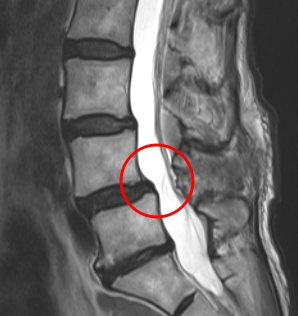

治療後

手術から1か月後、腰椎MRIを確認したところ、神経の圧迫を解消していることを確認しました。また左足の痛みと痺れは良くなったとのことだったのですが、お尻の右側に少し重みがあるとのことでした。この感覚は、神経損傷による後遺症と判断し、右L5にPRPを注入。術後3ヶ月目の検診時には、腰痛が10から0に、右下肢の痛みが10から2に、右下肢の痺れが10から1に。痛み止め薬を飲まなくても大丈夫なほどの改善効果が見られたため、さらに効果を高めようと、追加でPRPを注入しました。